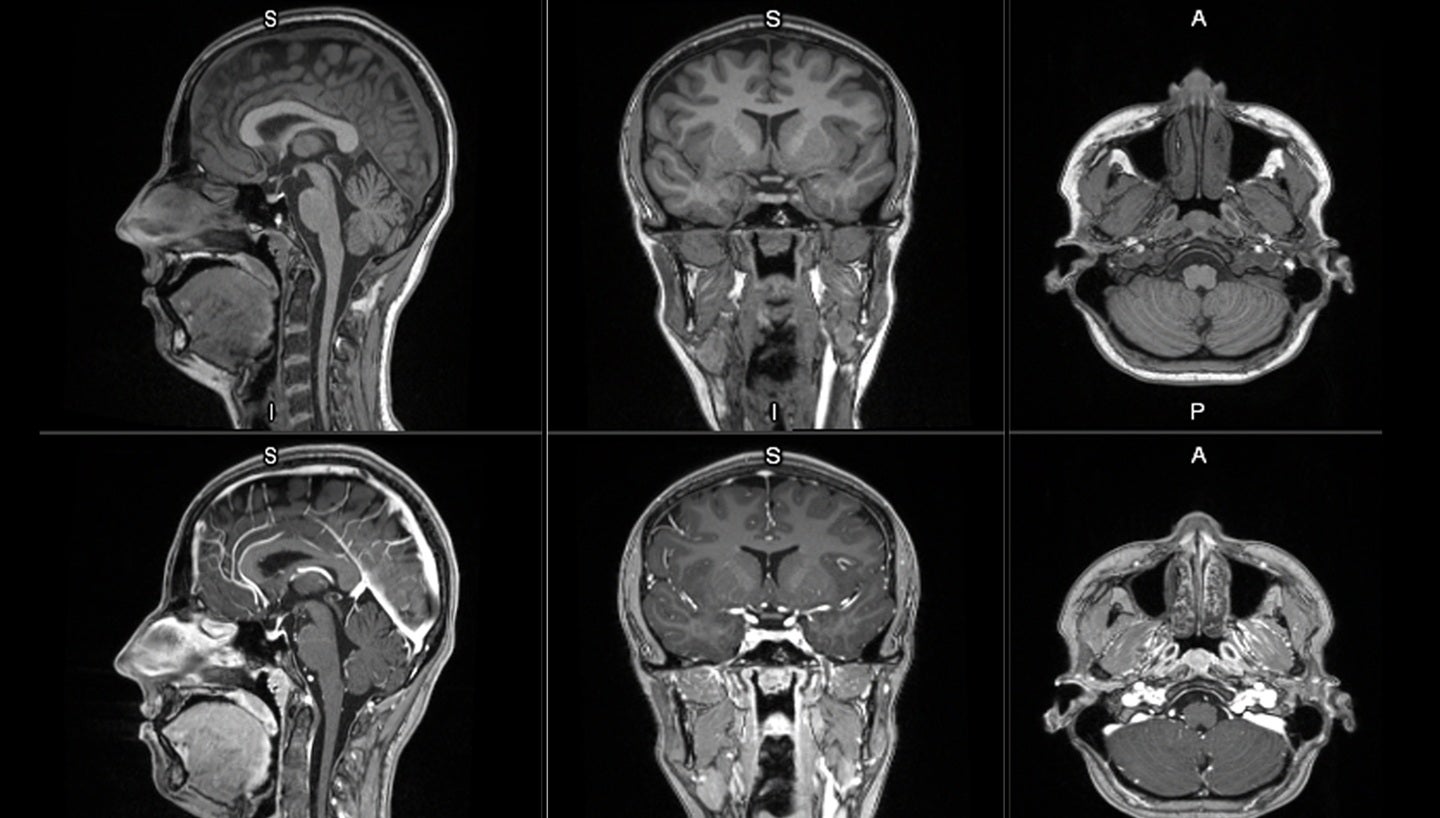

The LUMINA trial is evaluating the efficacy and safety of mangaciclanol for contrast-enhanced MRI of the central nervous system and body in adult and pediatric patients aged two years and older. Mangaciclanol is designed to improve the visualization of lesions with abnormal vascularity, offering comparable relaxivity to gadobutrol—a widely used gadolinium-based agent—while leveraging manganese, an essential element naturally regulated in the human body. Its macrocyclic structure aims to limit retention, addressing long-standing concerns about gadolinium deposition in tissues such as the brain and bones.

According to clinical trial registry information, the LUMINA study (NCT07472491) is actively recruiting participants and is sponsored by GE Healthcare. The trial’s objectives include assessing image quality, diagnostic accuracy, and safety profile compared to existing gadolinium-based agents. Early clinical data suggest mangaciclanol may provide similar diagnostic performance with a potentially improved safety profile due to the endogenous regulation of manganese and its reduced risk of accumulation.